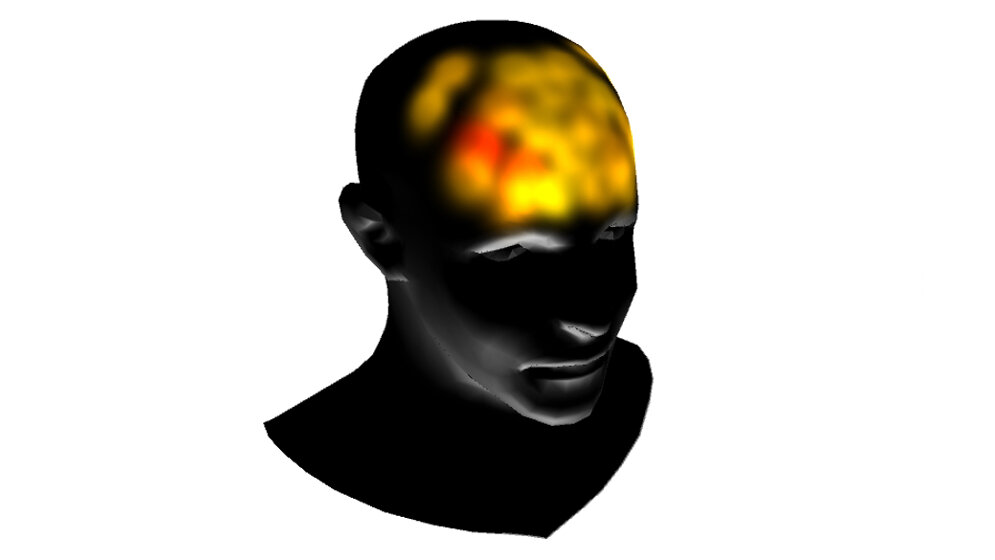

Die Forscher/-innen ließen die Versuchspersonen in einem Bewegungssimulator Platz nehmen und rotierten sie so, dass ihre Wirbelsäulen dabei vertikal zur Erdachse ausgerichtet waren. Genauer gesagt, erlebten die Probanden/-innen mehrmals zwei aufeinanderfolgende Rotationen, bei denen eine jeweils etwas intensiver war als die andere. Die Reihenfolge der kleineren und größeren Rotation war dabei jeweils zufällig und die Versuchsteilnehmer/-innen sollten beurteilen, welche der beiden Rotationen intensiver war. Während die Teilnehmer/-innen die Aufgabe durchführten, wurde der Blutfluss in den präfrontalen und parietalen Bereichen mit einer neuartigen Technik, der funktionellen Nahinfrarotspektroskopie (fNIRS), gemessen. Die Wissenschaftler/-innen nutzten diese Aufzeichnungen anschließend, um zu untersuchen, ob es möglich war, die Beurteilungen der Teilnehmer für jedes einzelne Rotationspaar vorherzusagen.

Bisher gibt es nur wenige Untersuchungen über Hirnaktivitäten von Probanden/-innen oder Patienten/-innen in Bewegung, da Messungen mit geläufigen neuronalen Bildgebungsverfahren, wie der Elektroenzephalographie (EEG) oder der funktionellen Magnetresonanztomographie (fMRI), durch Bewegungen des Körpers und elektromagnetische Inferenzen, wie beispielsweise elektrische Störsignale in Fahrzeugen, verzerrt werden. Dies ist bei fNIRS jedoch nicht der Fall. Infrarotlicht wird durch die Kopfhaut in das Hirngewebe gestrahlt, wodurch die Reflektion gemessen werden kann. Da die Lichtintensität des Infrarotlichts sehr gering ist, ist diese Methode nicht invasiv und daher harmlos. In den aktiven Hirnregionen steigen der Blutfluss und der Sauerstoffgehalt an (hämodynamische Reaktion), was mithilfe dieser Methode erfasst werden kann. Dadurch können Schlussfolgerungen über Aktivitäten in den betroffenen Hirnregionen gezogen werden.